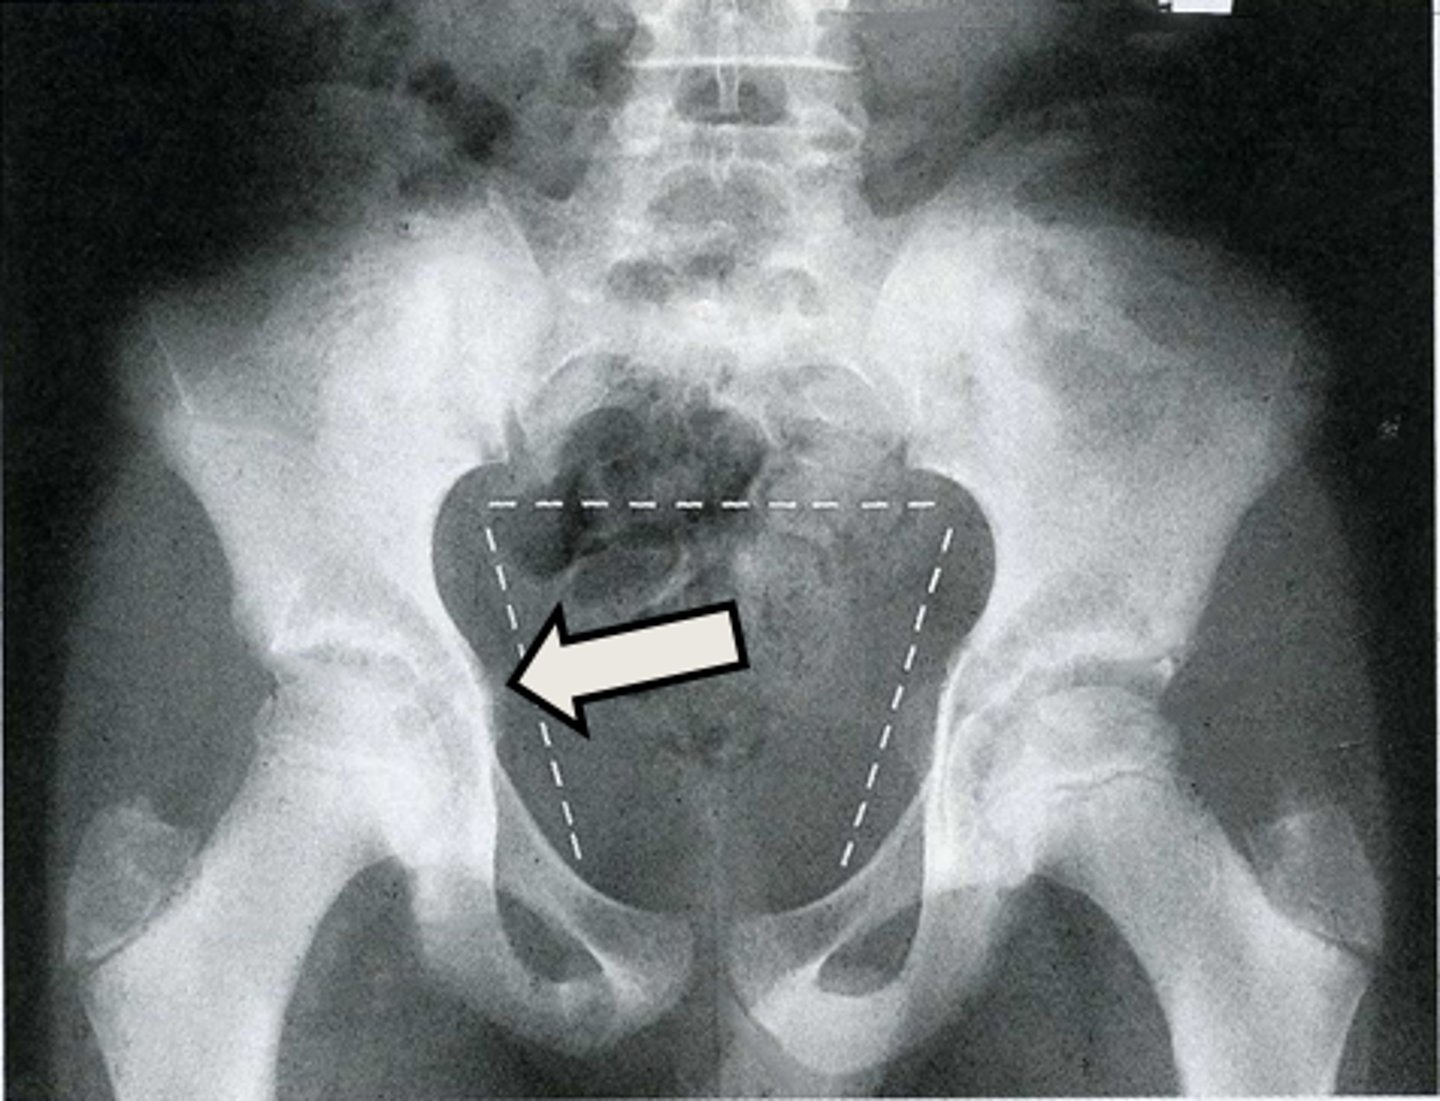

Axial bony pelvis CT

What is the image?

32

New cards

L ilium

What is indicated in the image?

<p>What is indicated in the image?</p>

33

L sacroiliac joint

34

R ilium

35

R sacroiliac joint

36

Sacrum